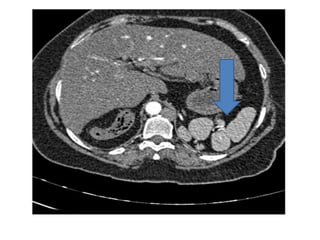

3. Metastases: Of all metastases 7% is seen in spleen.

Occurs genereally in presence of wide spread metastases

elsewhere. Lymphomatous involvement of spleen is

relatively common where there is splenic enlargement

without an identifiable focal abnormality.

These lesions are usually necrotic and are seen as low

density lesions on CT. They show ring enhancement on

contrast study.

On USG they most commonly appear as a hypoechoic

lesion, although can be iso- or hyperechoic.

Metastases on CT